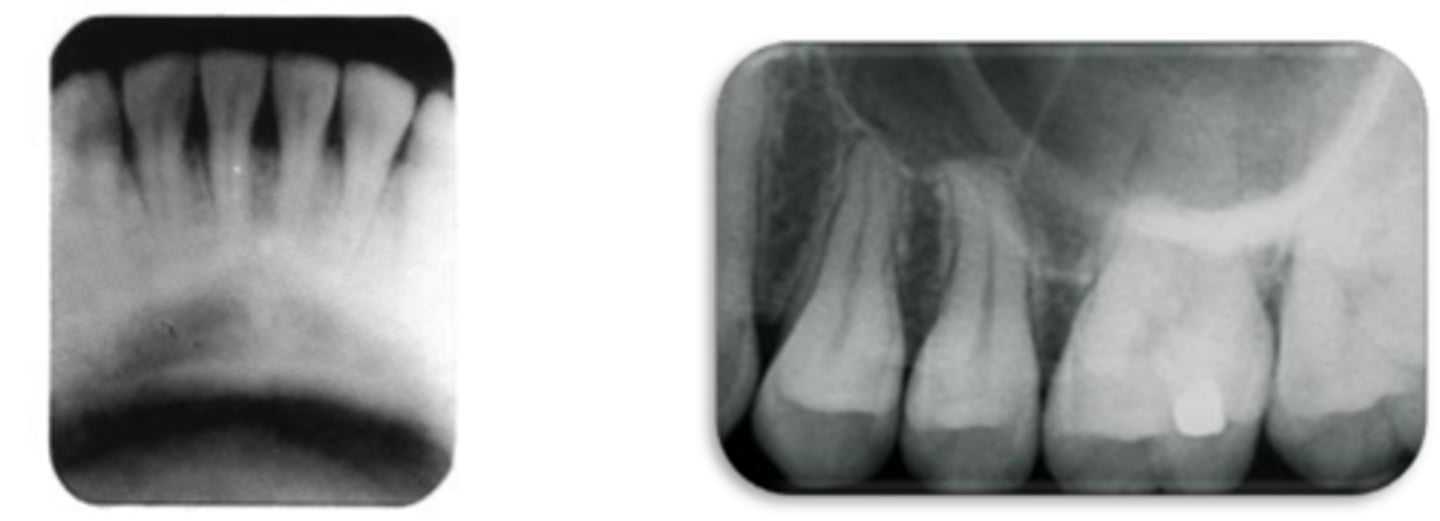

What type of dental radiograph?

Conventional Film

Digital Sensor